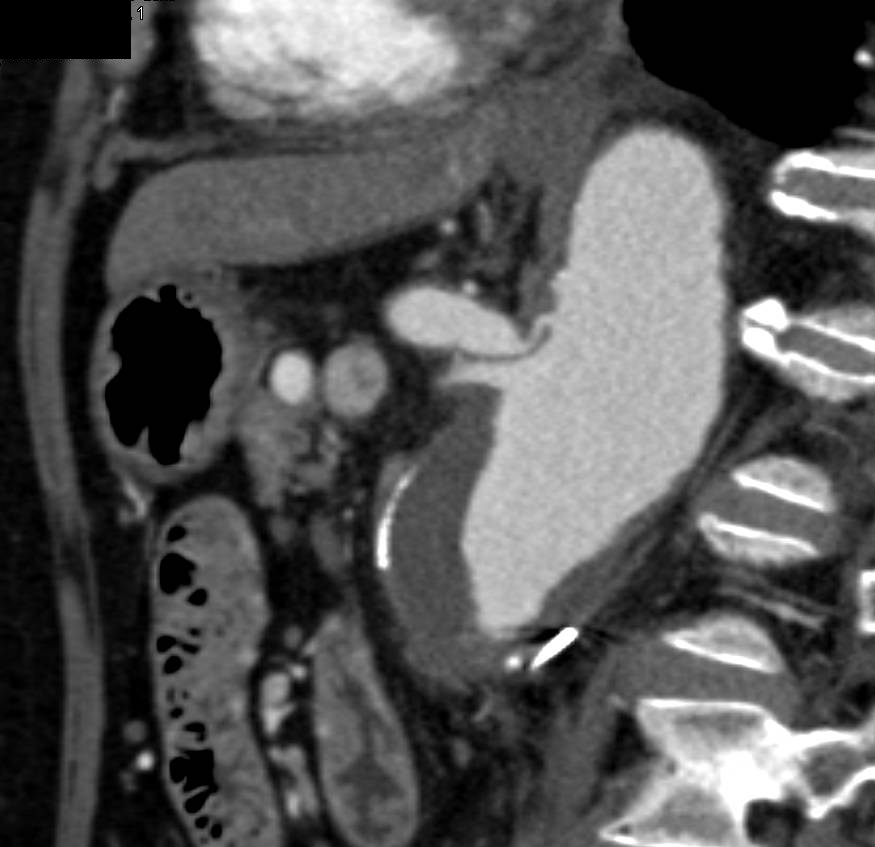

Midgut Volvulus with Ischemic Bowel